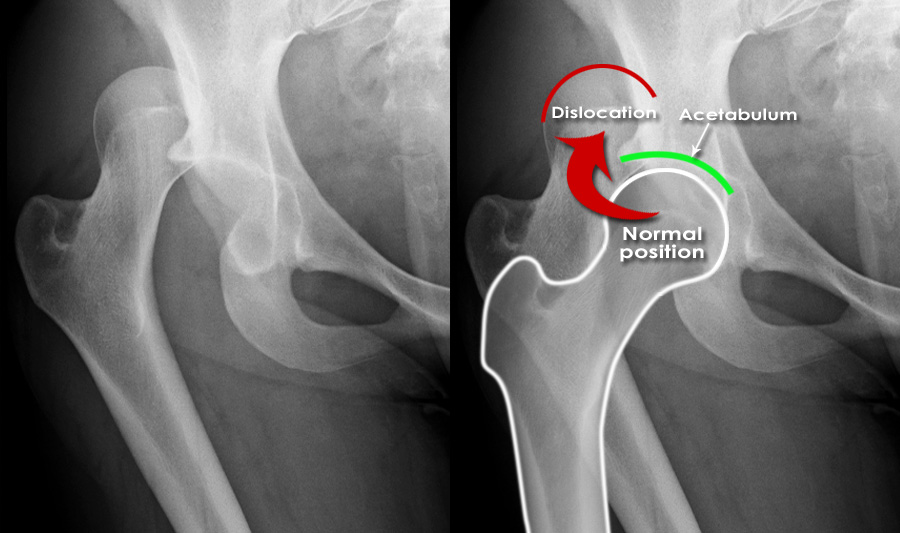

Hip fractures and dislocations are significant orthopaedic injuries that can severely impact your mobility and overall quality of life. A hip fracture occurs when a break develops in the upper part of the femur (thigh bone), often due to trauma, falls, or weakened bones from conditions like osteoporosis. A hip dislocation happens when the femoral head (the ball) is forced out of its socket in the pelvis, typically caused by high-impact trauma like car accidents or severe falls.

Both conditions require prompt medical attention. A hip fracture often necessitates surgery to realign or stabilise the bone, while a hip dislocation requires immediate reduction to restore the ball to the socket. Early treatment can prevent further damage, reduce the risk of complications, and support recovery.

- X-Rays: X-rays are used to identify fractures or dislocations in the hip joint. They also reveal the type and severity of the fracture.